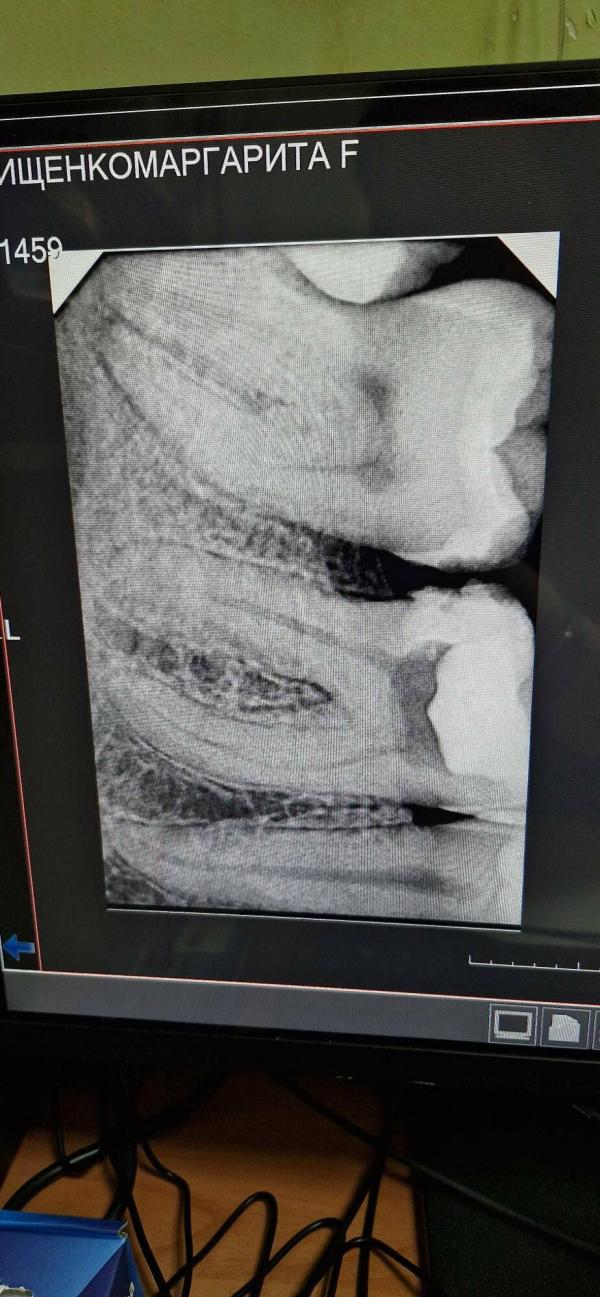

Девочки подскажите у кого был пародонтит, долго ли может болеть зуб, вчера поставили лекарство, острая боль не утихает. Должно ли быть так или бежать в платную клинику, т.к. наши врачи сказали, что до вечера боль должна успокоиться?